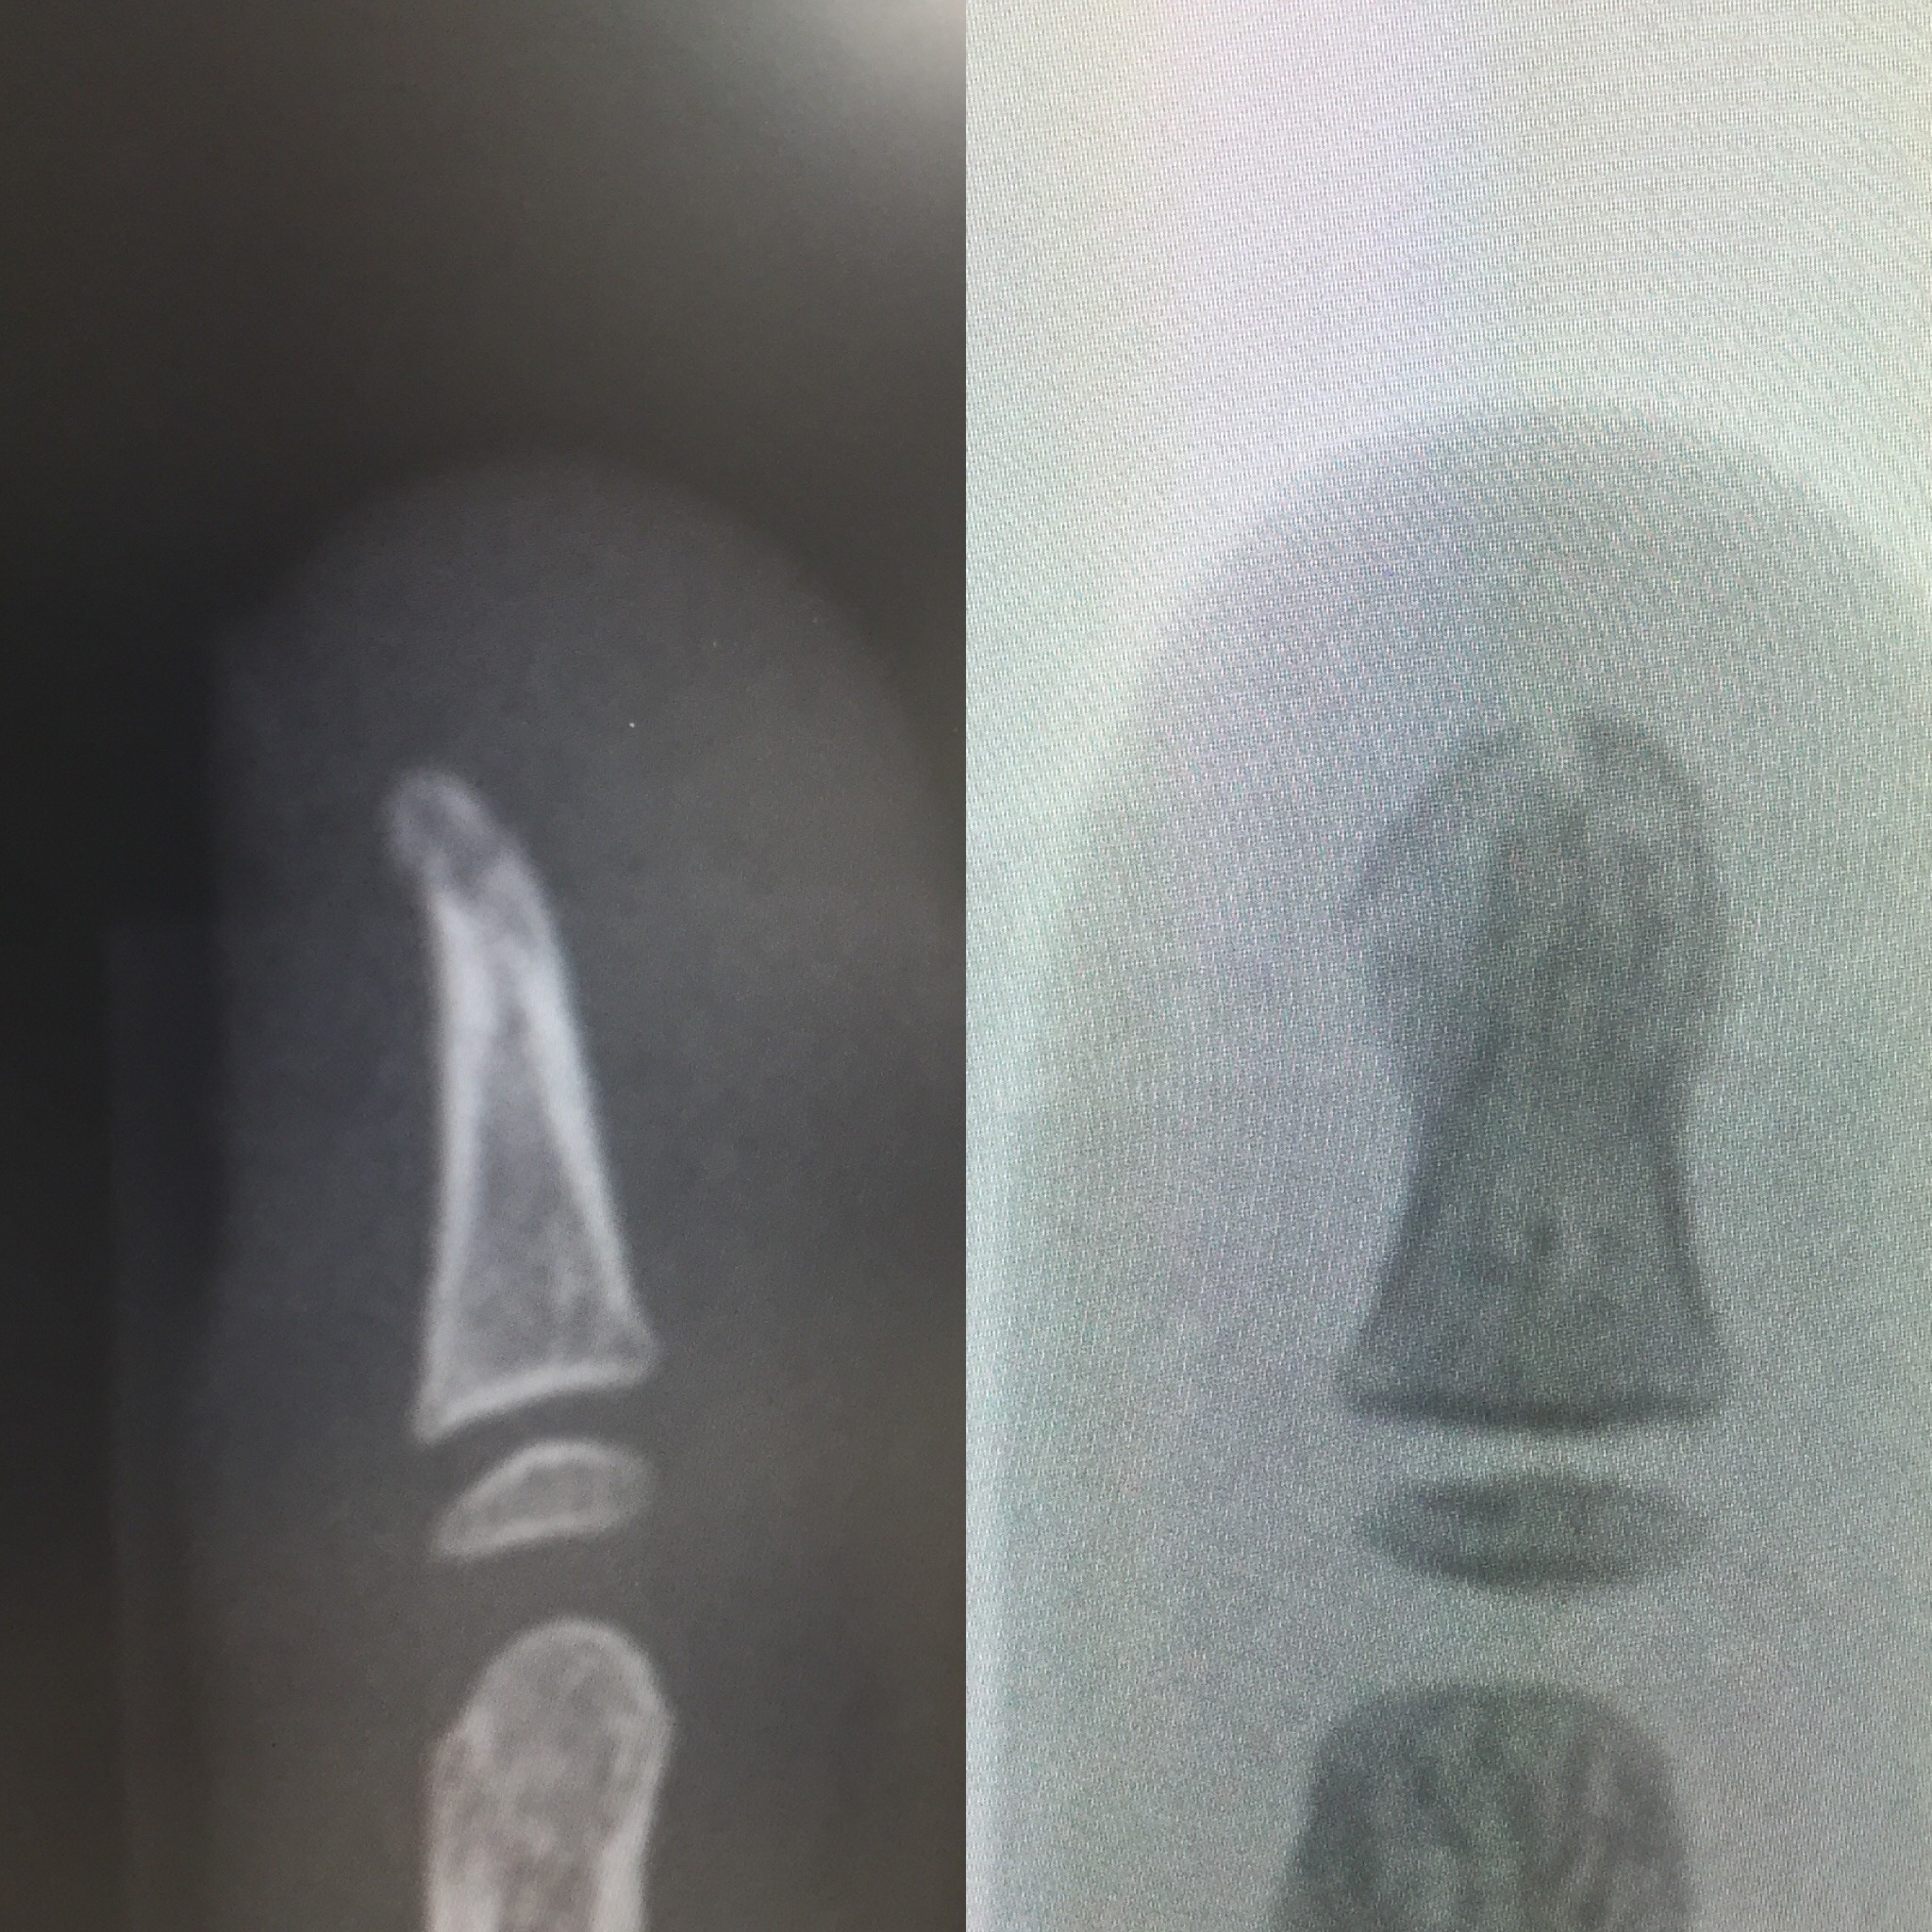

大チビのレントゲンを撮ってもらうと

先っぽがやはり折れてました><

施設内のロビーで指を確認してみると

爪の根元の皮膚が裂けまあまあの流血![]()

表側は内出血&腫れ

これはひどい、折れとるかもしれん

折れてる可能性があるが

技師が居ないのでレントゲンは撮れないとのことだったので

折れてるのを前提に添え木の処置をしてもらいました